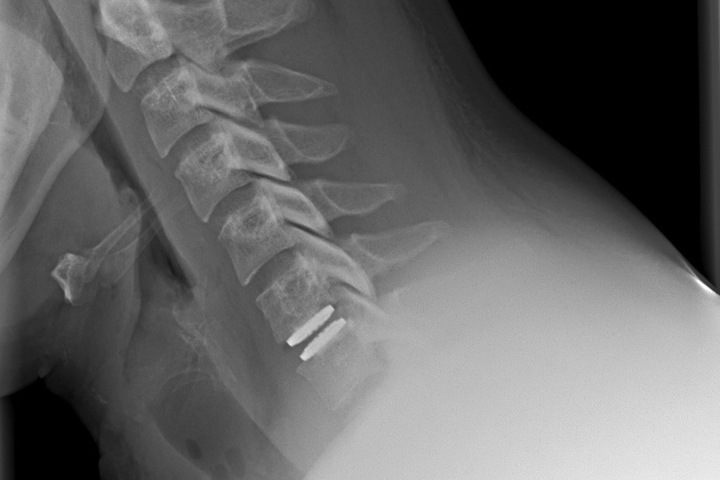

Медицинские решения: Пластина для позвоночника М6